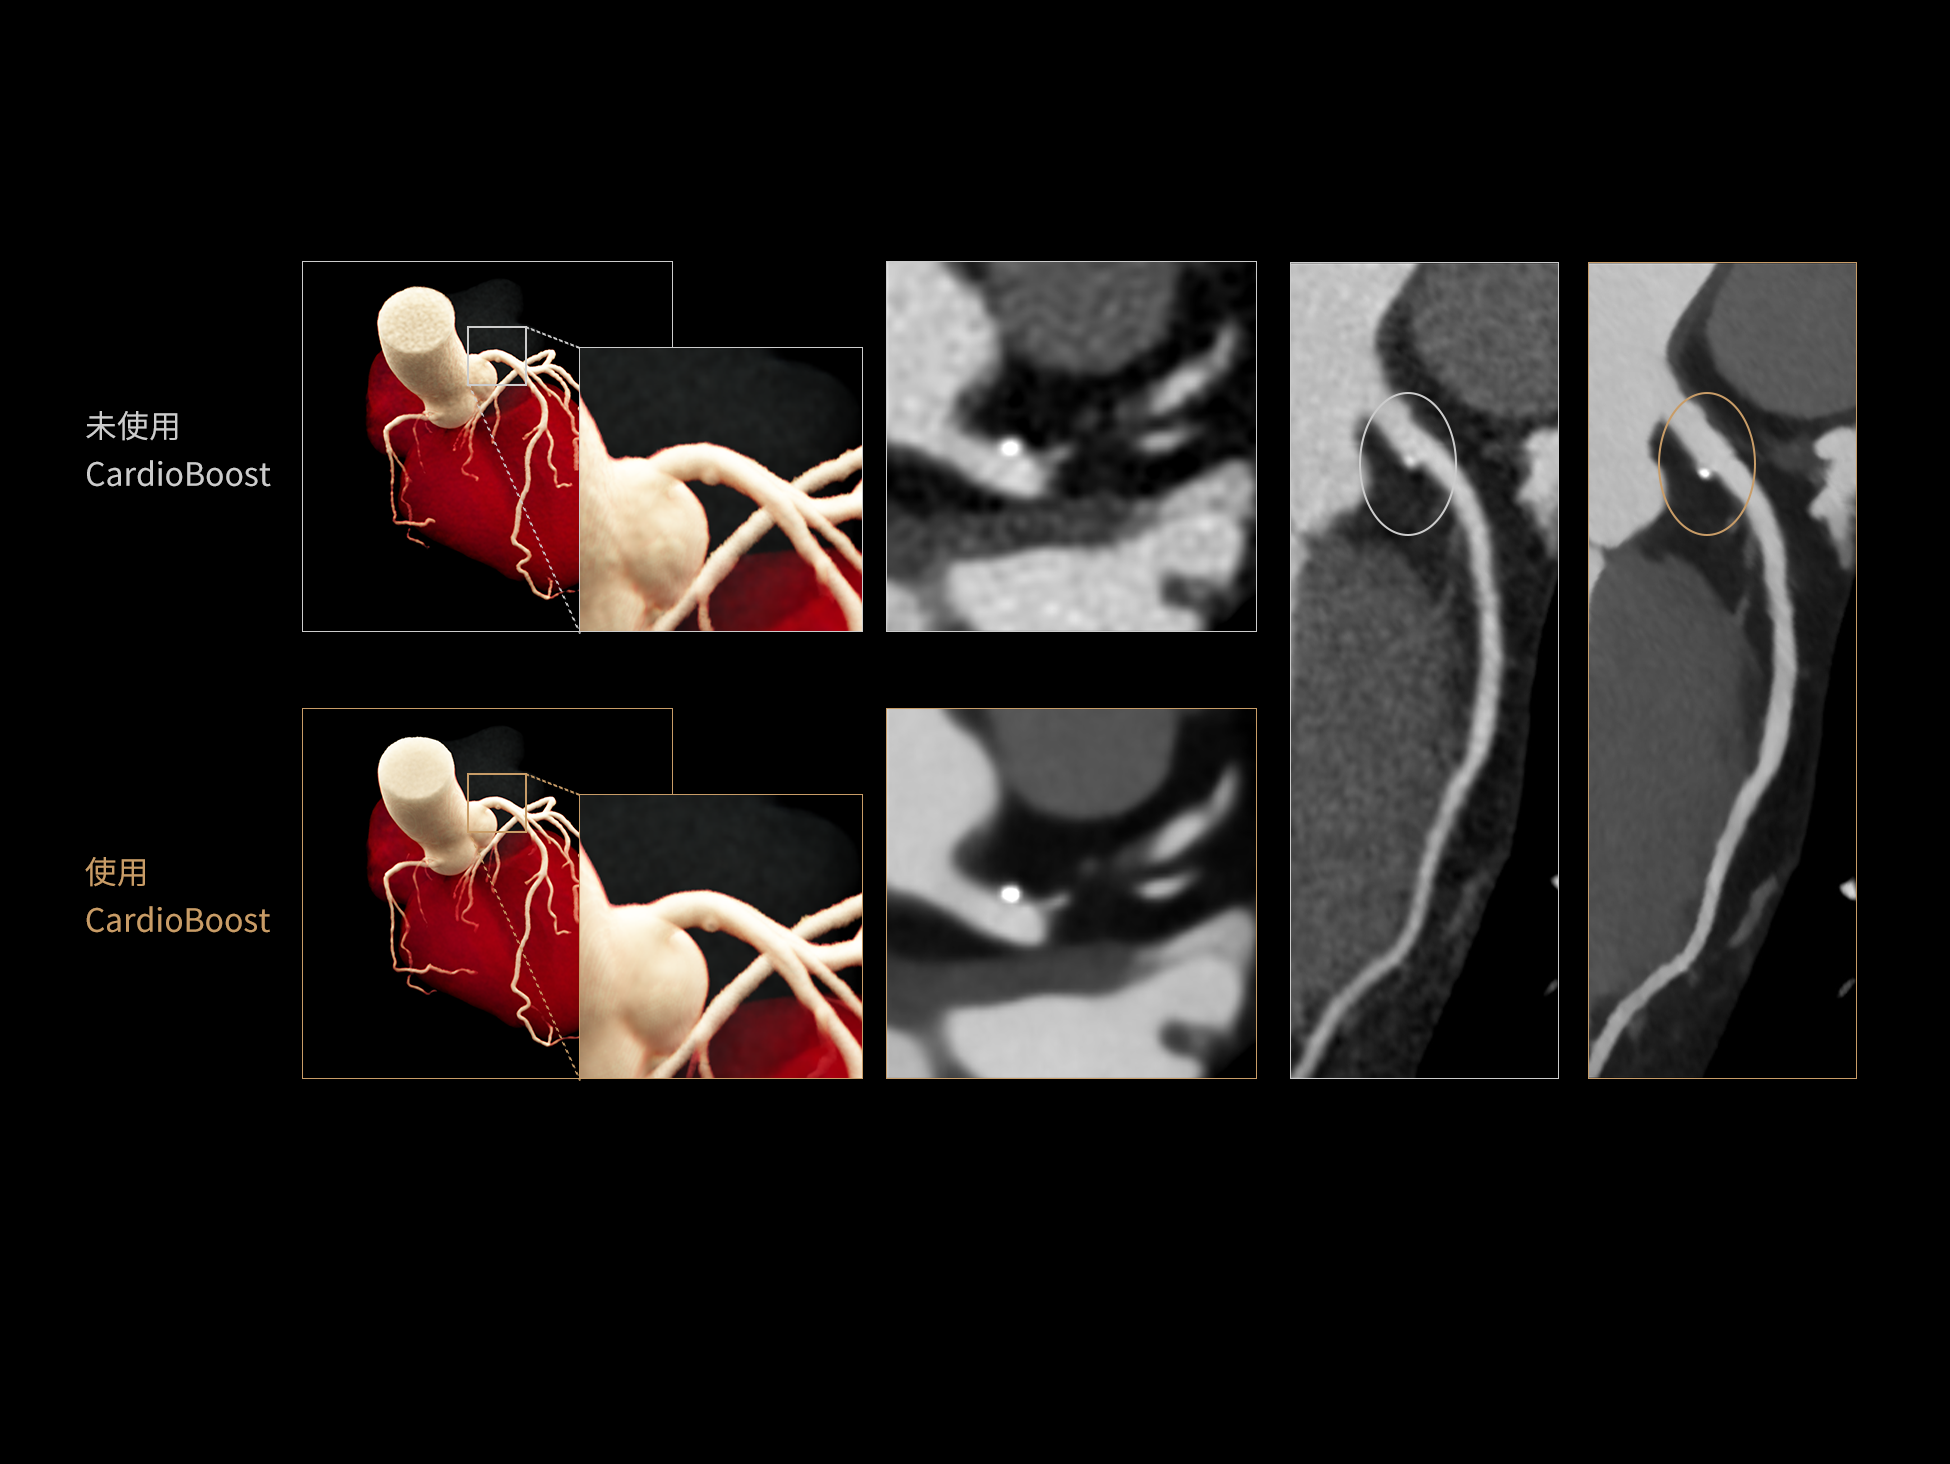

相同低对比度分辨率下

辐射剂量减少